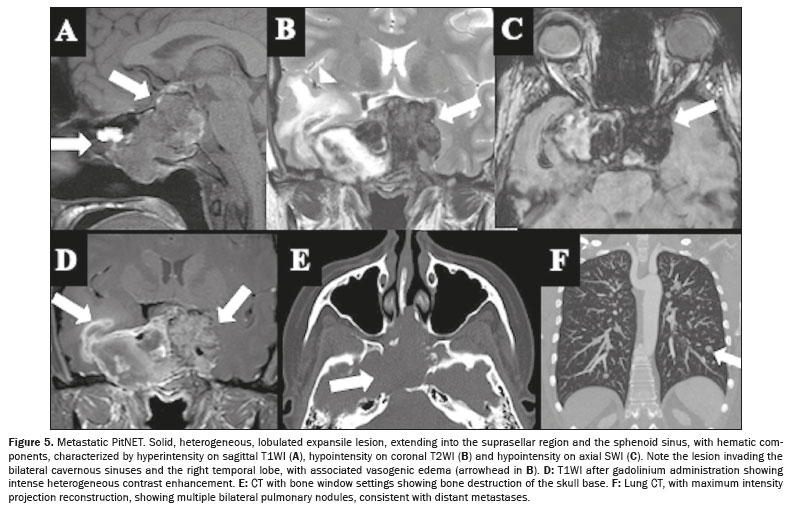

Pitfall and differential diagnosisPituitary carcinomaMetastatic PitNETs, as pituitary carcinomas are currently referred to in the 5th edition of the WHO classification

(5), are rare pituitary neuroendocrine tumors that spread to lymph nodes, distant organs, or via discontinuous central nervous system dissemination, accounting for only 0.1% of all pituitary tumors

(64). Previously classified as “pituitary carcinomas” in earlier WHO editions, the 5th edition of the WHO classification now designates all PitNETs as malignant, using the term metastatic PitNETs for those with confirmed metastases

(5). These lesions are histologically indistinguishable from typical PitNETs. Most originate as invasive lactotroph or corticotroph tumors and subsequently metastasize, in which cases the average survival is less than four years

(65).

Some pituitary tumors destined to become carcinomas show early aggressive behavior (Figure 5), with rapid recurrence and progression after initial surgery, while others evolve into carcinomas only after many years. Notably, pituitary carcinoma can remain undetected for a long time despite persistently elevated biochemical markers and no visible sellar tumor, as illustrated by cases in which distant metastases, such as GH-immunopositive cervical adenopathy, reveal the diagnosis

(64).